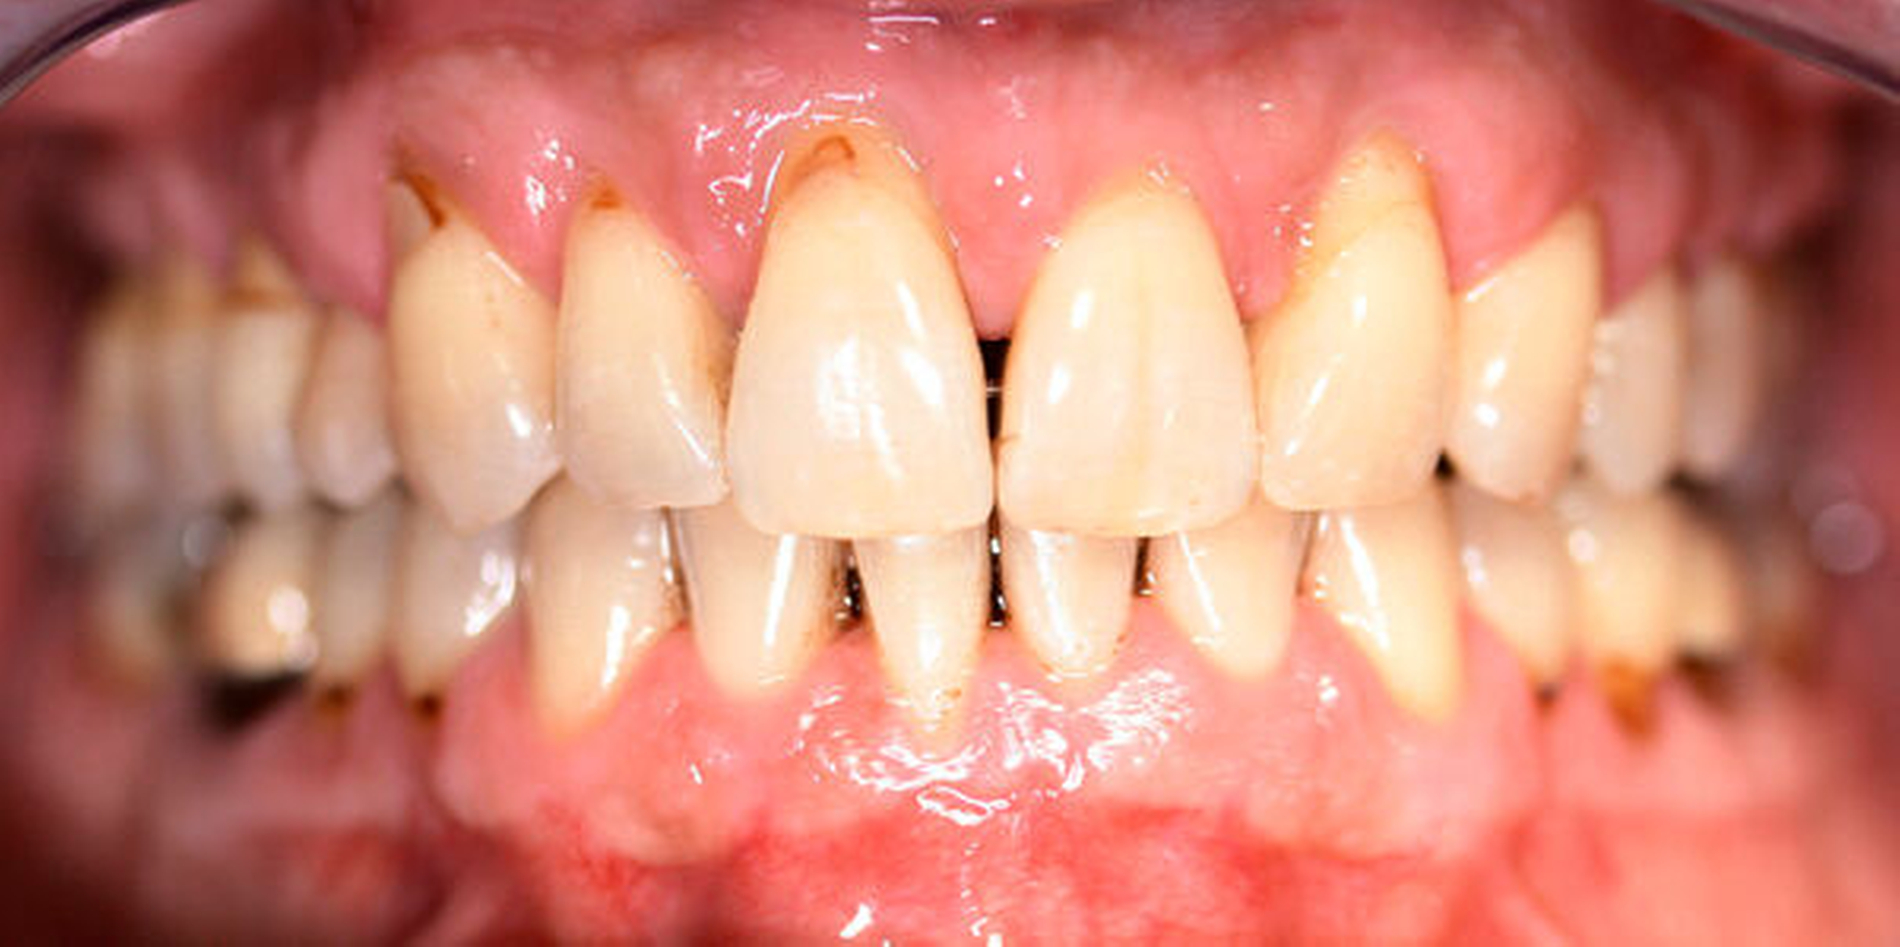

Anamnestisch lagen keine Besonderheiten vor. Es ist jedoch zu vermerken, dass ein regelmäßiger Alkohol-, Koffein- und Nikotinkonsum zugrunde lag. Intraoral zeigte sich ein bereits konservierend versorgtes permanentes Gebiss mit aktivem und inaktivem kariösen Geschehen. Große Anteile der Zahnhälse lagen nach Zahnfleischrückgang in Kombination mit Knocheneinbrüchen frei. Zahn 27 wurde bereits extrahiert.

Eine Beurteilung der parodontalen Situation an Zahn 11 offenbarte mesial und distal Sondierungstiefen von jeweils 6 mm.

Kieferorthopädisch imponierte beidseits eine neutrale Verzahnung bei einem tiefen Biss von 5 mm – bedingt durch die Verlängerung beider Frontzahngruppen. Besonders Zahn 11 zeigte eine erhebliche Verlängerung und Protrusion mit einer sagittalen Frontzahnstufe von 5 mm. Sowohl die Frontzähne im Ober- als auch im Unterkiefer wiesen eine lückige Beziehung zueinander auf (Abbildung 1).